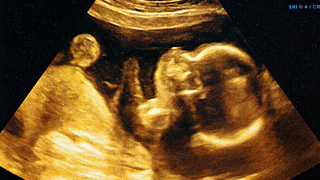

Why Babies Grow in Spurts Instead of a Straight Line Inside the WombOnce you get pregnant, your baby’s growth doesn’t always happen in a consistent manner. Rather, they grow in spurts, periods of rapid development followed by slower phases. This is a usual pattern and crucial for healthy development. Knowing why babies follow such a growth pattern during pregnancy can make you feel calmer during ultrasounds. It also helps you understand what to expect about your baby’s size and weight. It can also assist you in taking better care of yourself, both physically and emotionally.